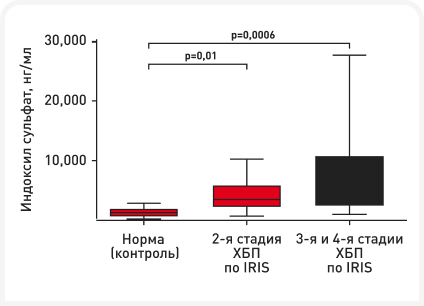

В ветеринарии информации о микробиоме, уремических токсинах и их связи с болезнью почек относительно немного, но про кошек известно немного больше. По сравнению со здоровыми кошками (≥ 8 лет), у кошек с ХБП описан дисбиоз, характеризующийся снижением разнообразия и богатства фекальной микробиоты по данным секвенирования гена 16S рРНК (9). Кроме того, в системном кровотоке у кошек с ХБП накапливаются уремические токсины, вырабатывающиеся в кишечнике. При ХБП у кошек показано значительное повышение уровней IS (Рисунок 5) соответственно прогрессированию заболевания (10–12). В одном исследовании концентрации pCS между группами здоровых кошек и кошек с ХБП статистически значимо не различались, наиболее высокие концентрации были отмечены у кошек с ХБП (9).

Интересно, что даже у кошек с ХБП 2-й стадии по IRIS концентрация уремических токсинов была значительно выше, чем у кошек из контрольной группы, что означает, что этот дисбаланс возникает в процессе заболевания относительно рано.